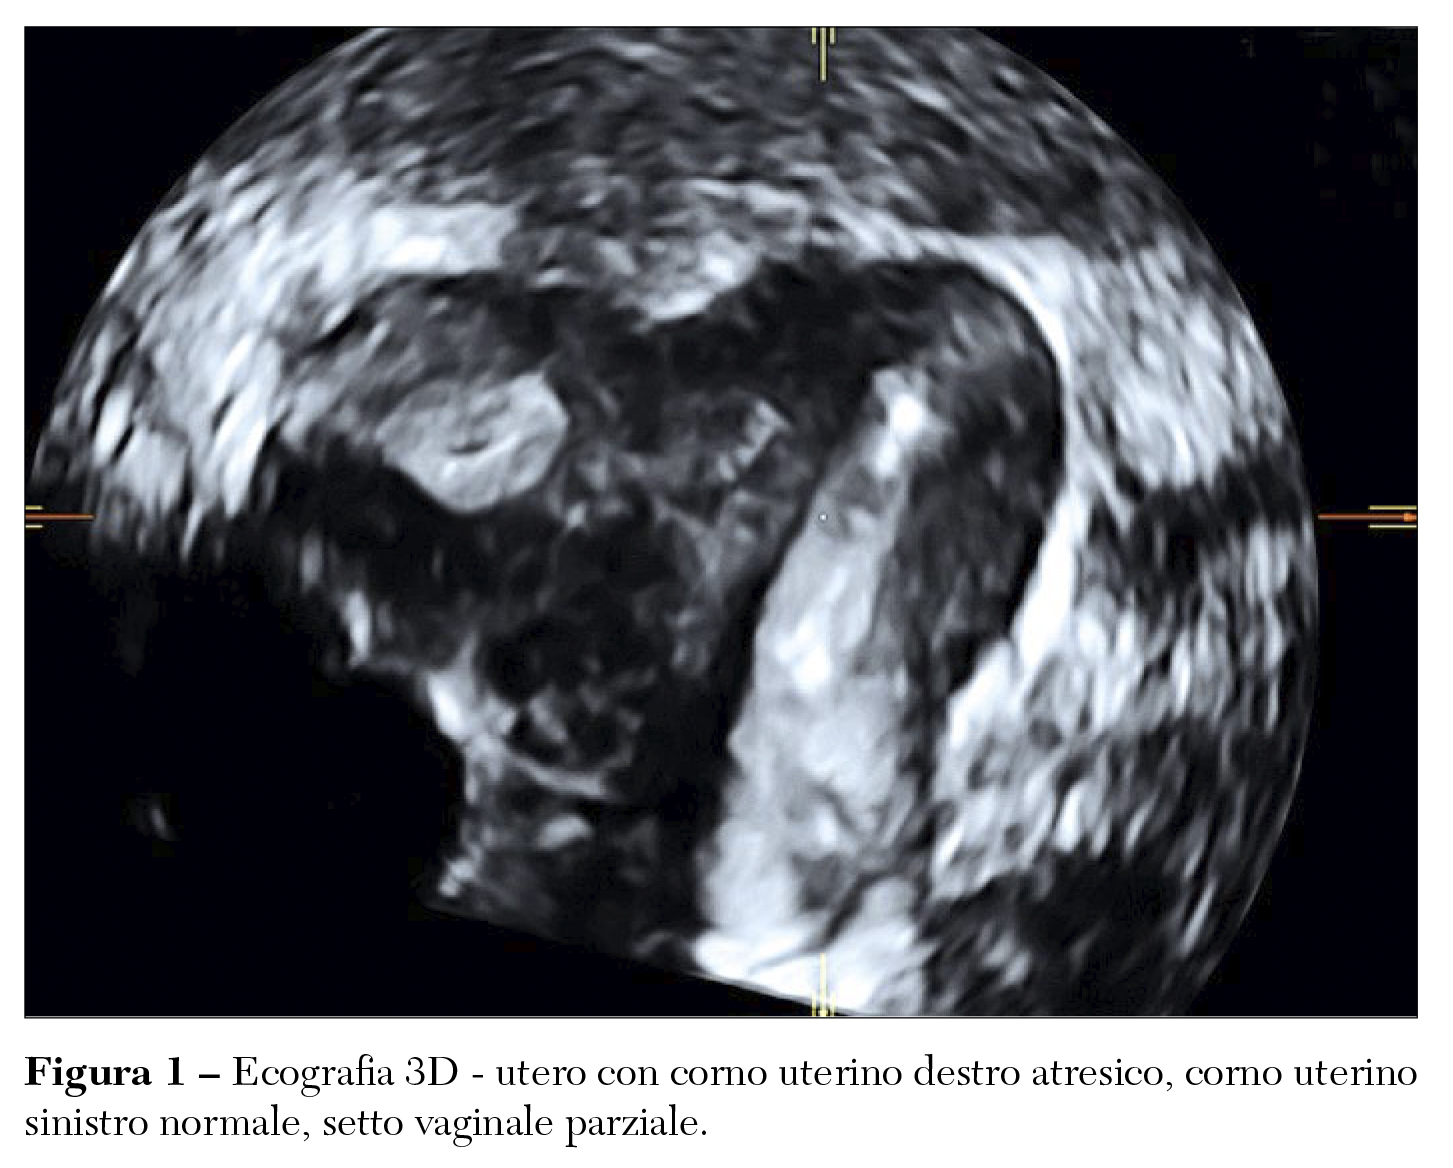

L’ecografia tridimensionale (3D) è raccomandata, invece, in caso di sospetto di anomalie genitali femminili in pazienti “sintomatiche” e in qualsiasi donna asintomatica sospettata di avere un’anomalia dalla valutazione di routine. Negli ultimi anni l’ecografia trans vaginale tridimensionale (3D) ha portato un enorme miglioramento nello studio dell’anatomia uterina. La scansione utilizzata per acquisire il volume uterino è quella longitudinale e deve essere selezionata la sezione coronale. Inoltre, è bene eseguirla in fase luteale tardiva al fine di sfruttare la maggiore rifrangenza endometriale, che aiuta a definire meglio sia il contorno del fondo sia la volumetria delle due cavità in cui l’utero potrebbe essere suddiviso. (Figure 1, 2).